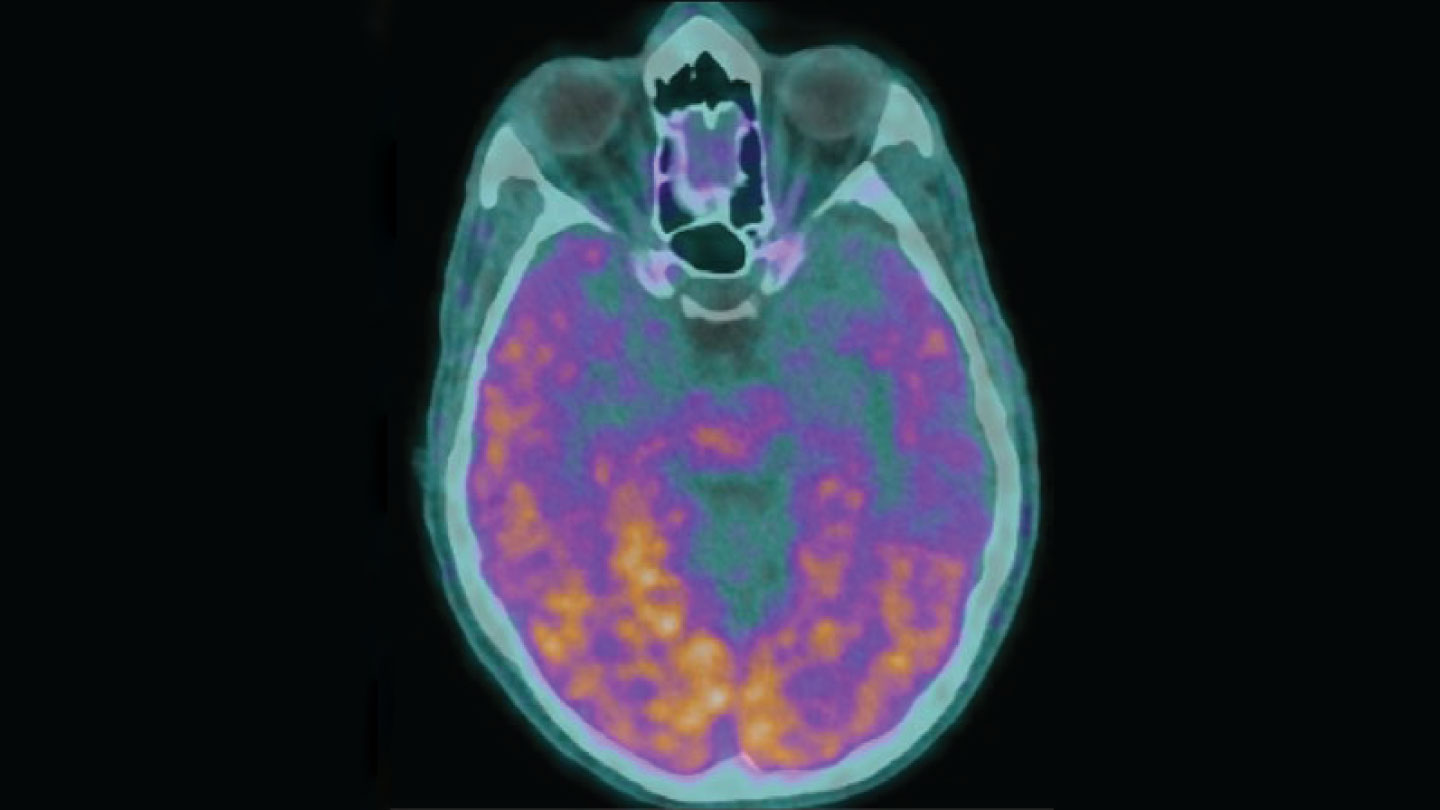

Transmissible Alzheimer’s?

Alzheimer’s disease is not contagious in everyday life, but under extremely rare conditions, it may spread from one person to another (SN: 2/24/24, p. 6). Five people who in childhood received contaminated growth hormone injections later developed early-onset Alzheimer’s — most likely because the hormones were tainted with amyloid-beta, a protein whose buildup is linked to the disease, researchers say. But it’s not yet clear whether the growth hormones are to blame, other experts note. Perhaps the health conditions that those hormones were meant to treat or other medical procedures led to the development of Alzheimer’s in these patients.